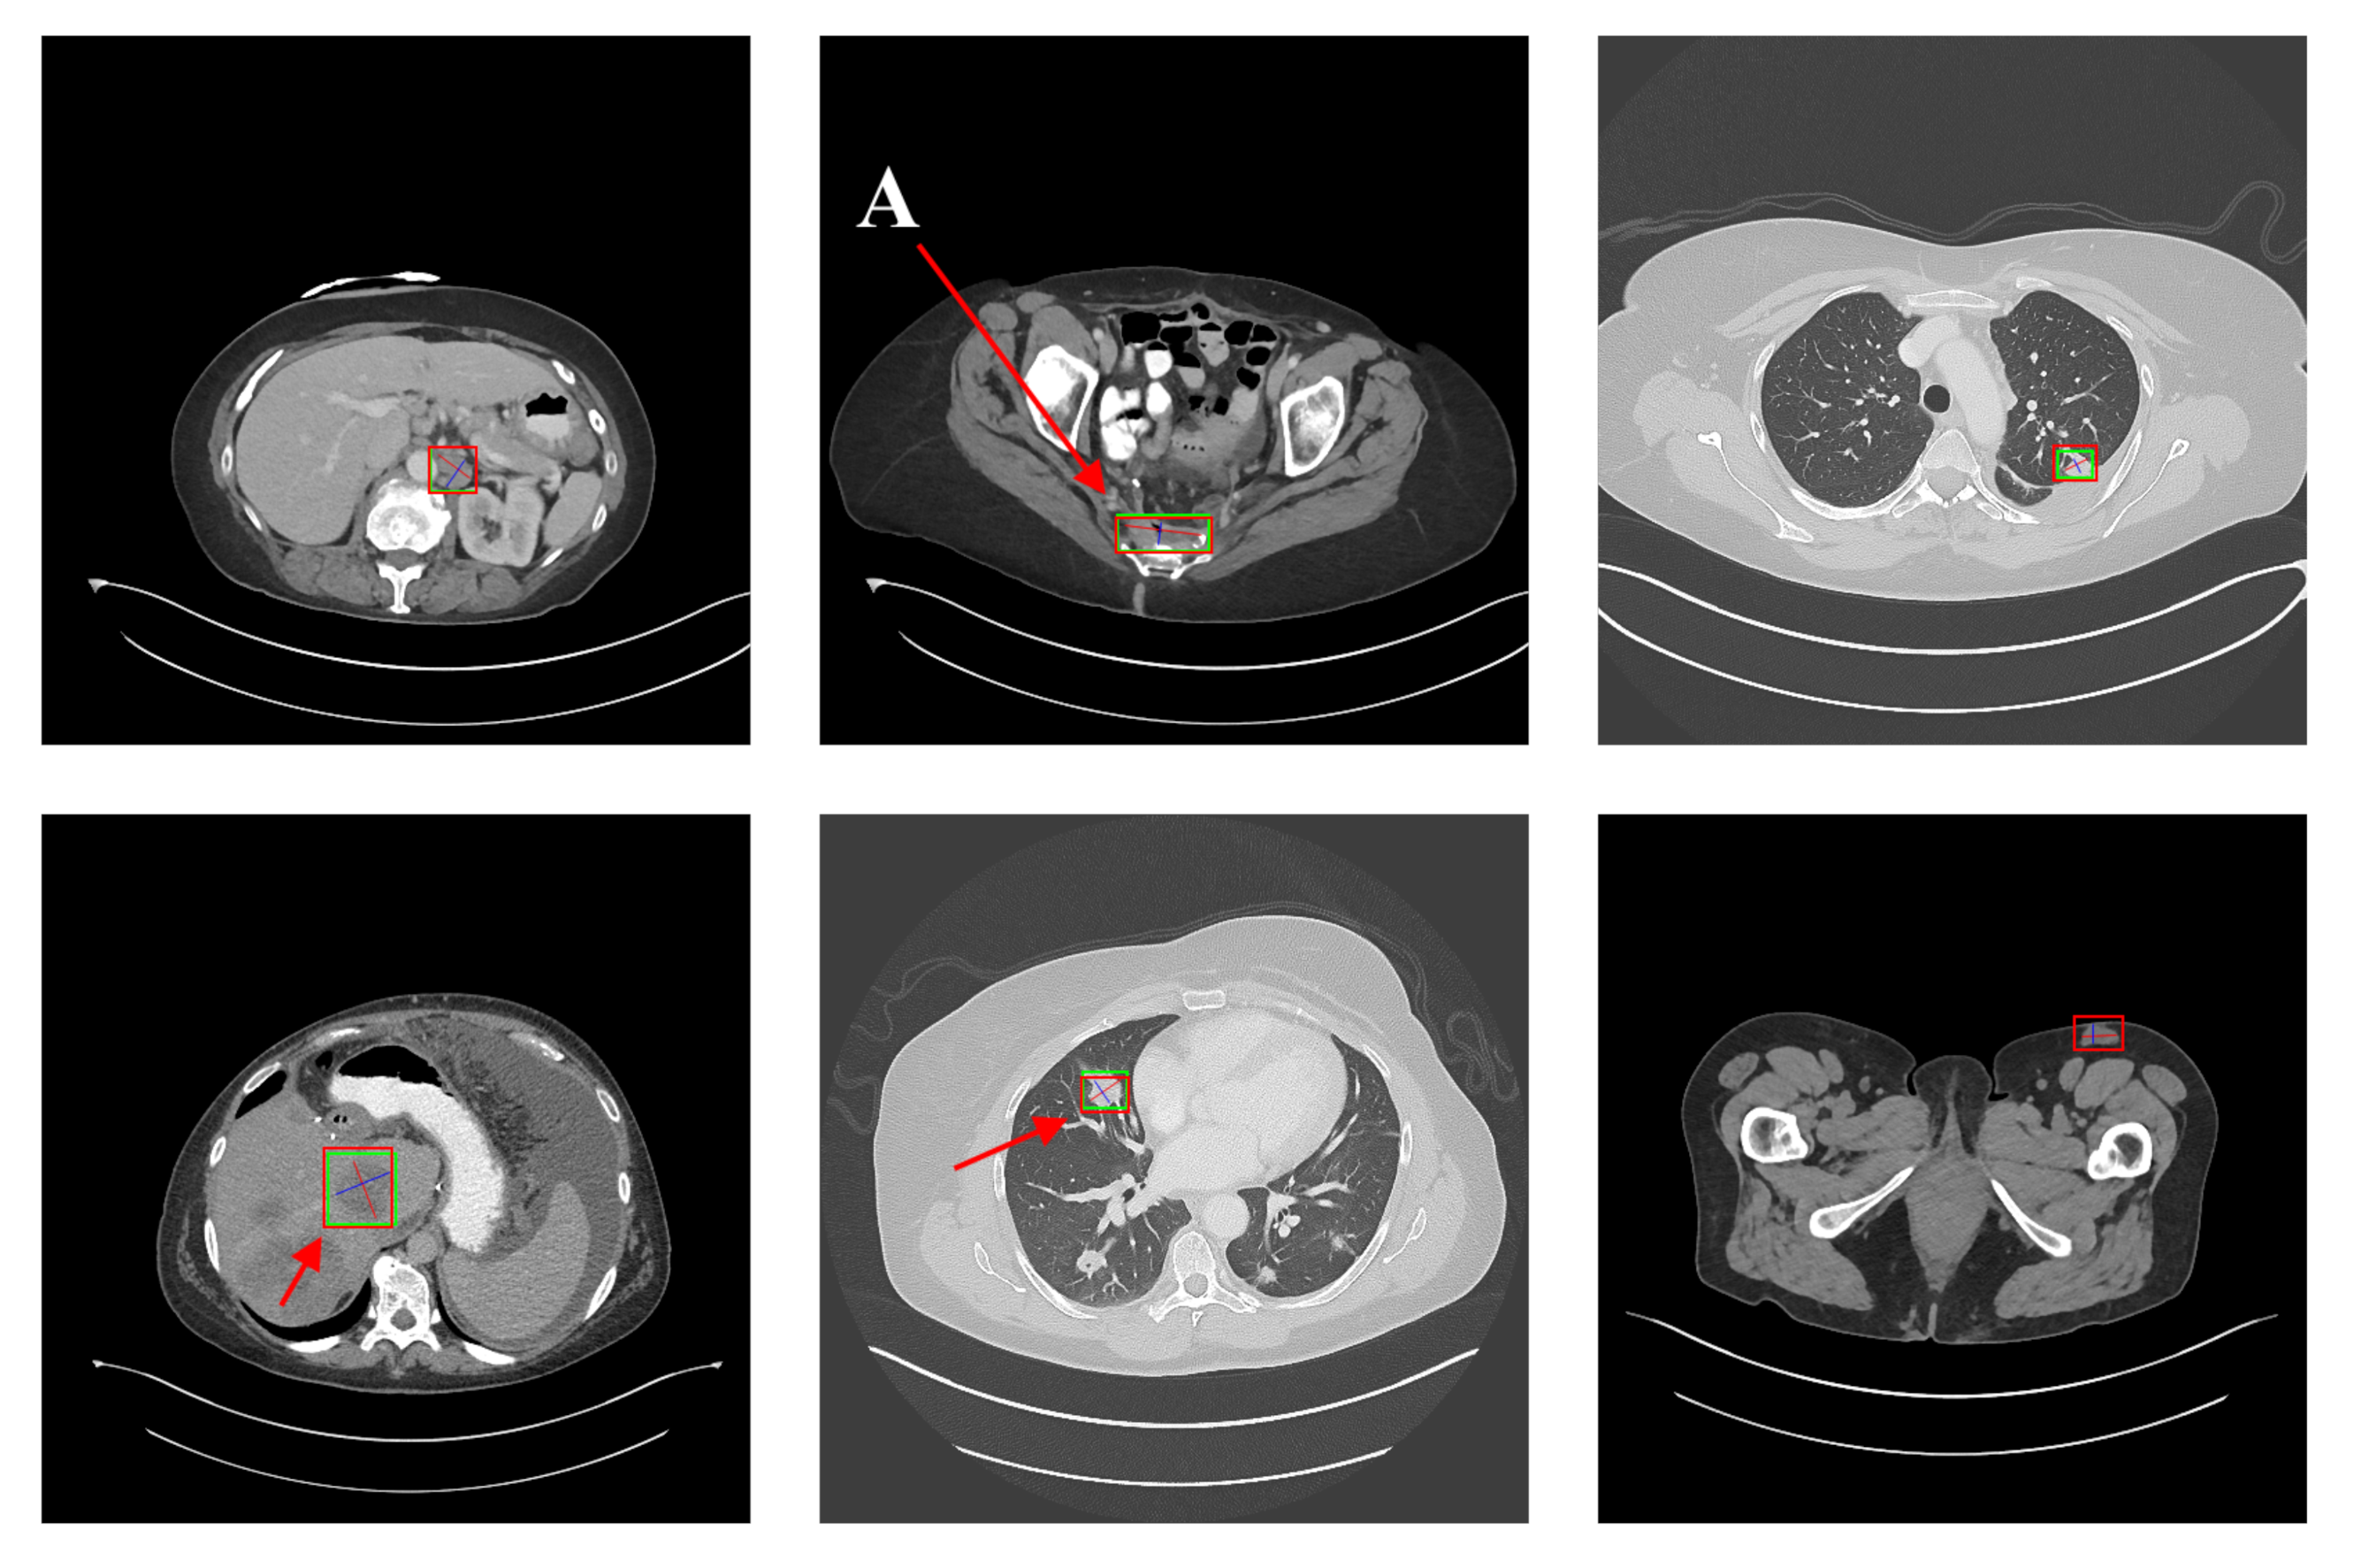

5.2. Detection Results

For further comparison, we extracted six images from the CT image series of DeepLesion. These images were taken from different sites of lesions and different areas of lesions, showing the detection results of the comparison model as comprehensively as possible. Figure 10, Figure 11, Figure 12, Figure 13, Figure 14, Figure 15, Figure 16, Figure 17, Figure 18 and Figure 19 show the detection results. All green boxes represent ground truth; red boxes denote predicted bounding boxes. It can be seen that Faster-RCNN performs very poorly on small lesions and lesions that are not easy to identify, while YOLO v3, YOLO v4, and SSD series perform relatively well. However, the aspect regression of the bounding box at small lesion locations is still not accurate. On the other hand, EfficientDet, Mask-RCNN, and YOLO v5 perform relatively well and detect lesions accurately. This may be related to the attention extraction module in these networks.

Figure 10.

The detection results of YOLO v3 in the DeepLesion dataset. The green box marks the location of the lesion.

According to Figure 10, Figure 11, Figure 12, Figure 13, Figure 14, Figure 15, Figure 16, Figure 17, Figure 18 and Figure 19, the proposed model produces the most comprehensive detection results compared to other models. However, there are still a few cases where the shortcomings of SGDN can be seen: the arrows in Figure 19 show that our model is still not accurate at the edge of the lesion. In addition, from these figures, we can see that all the comparison models perform very poorly at the site of arrow A. The difference between the predicted box and the ground truth given by our model at arrow A is the largest compared to other recognition results.